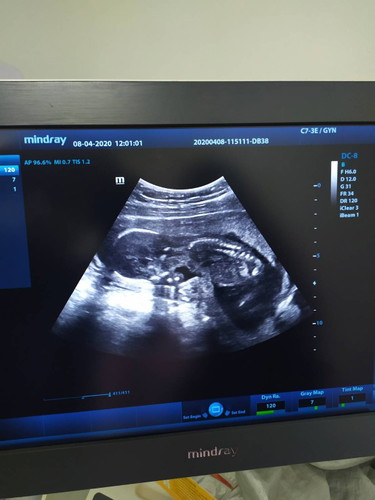

อันนี้ซาวน์ตอน17week

ช่วยดูหน่อยค่ะดูไม่ออกเลยลูกอยู่ตรงไหน

น้องคว่ำอยู่ค่ะ

คว่ำหน้าปะคะ